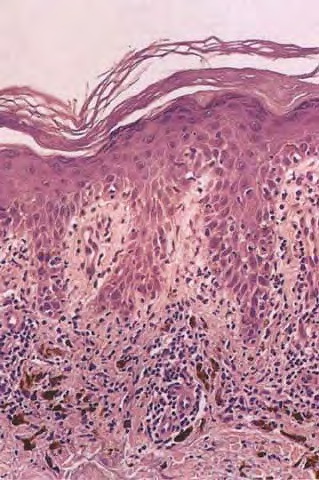

Subacute cutaneous lupus erythematosus = الذئبة الحمامية الجلدية تحت الحادة